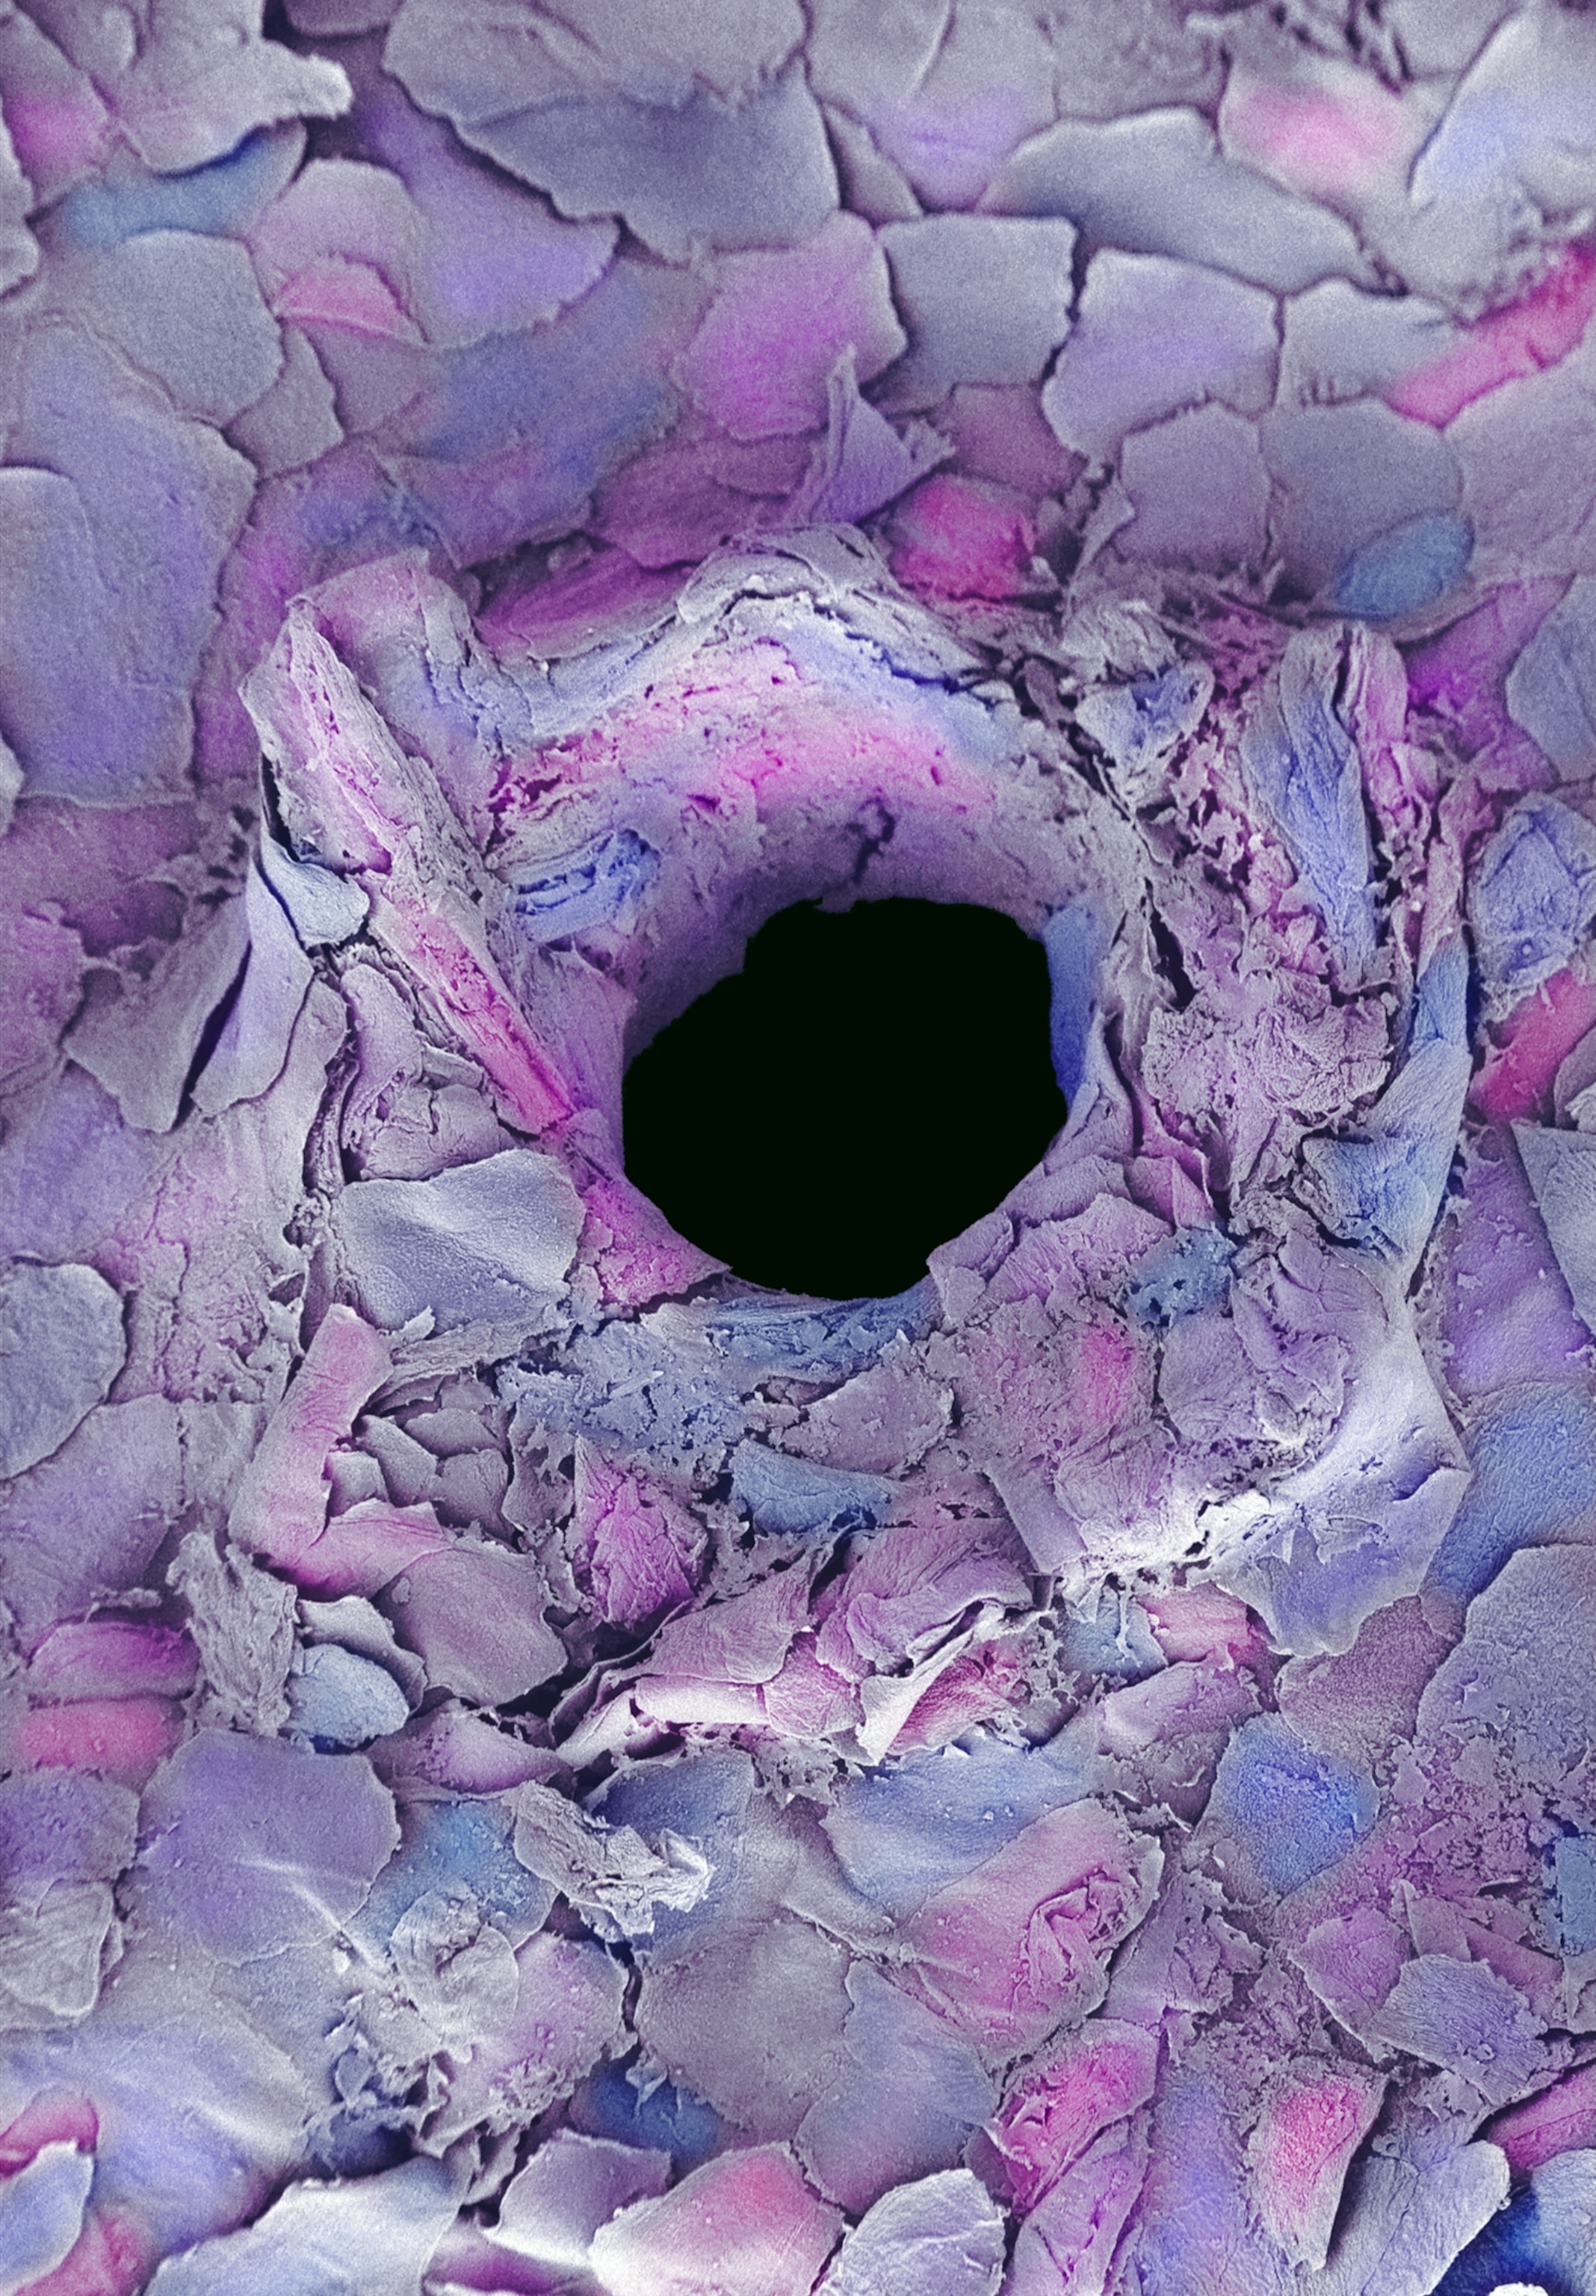

This image is a colored scanning electron micrograph of the hole created by tattoo needle in the epidermis, or top layer, or human skin. To make tattoos permanent, tiny needles are used to punch through the top layer of the skin and into the next layer (dermis).

Anne E. Weston, Science Photo Library